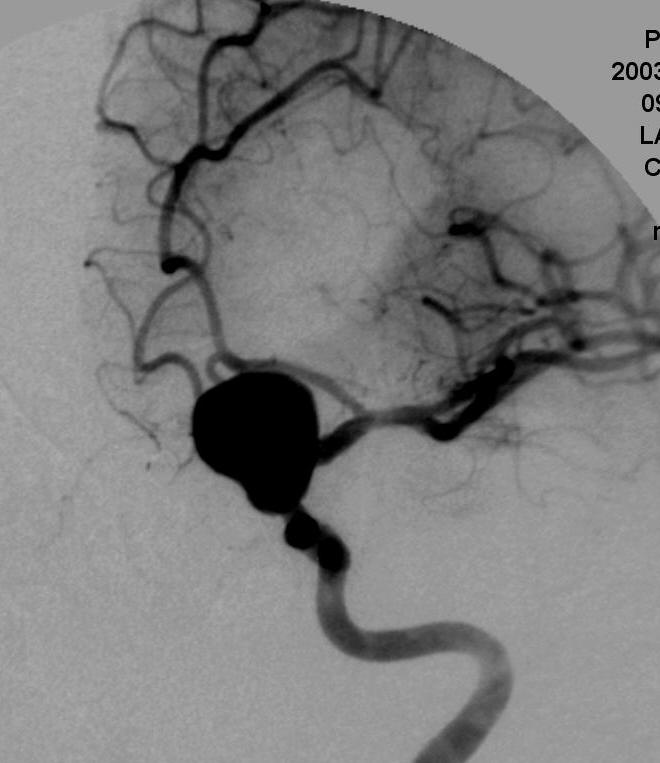

病例1